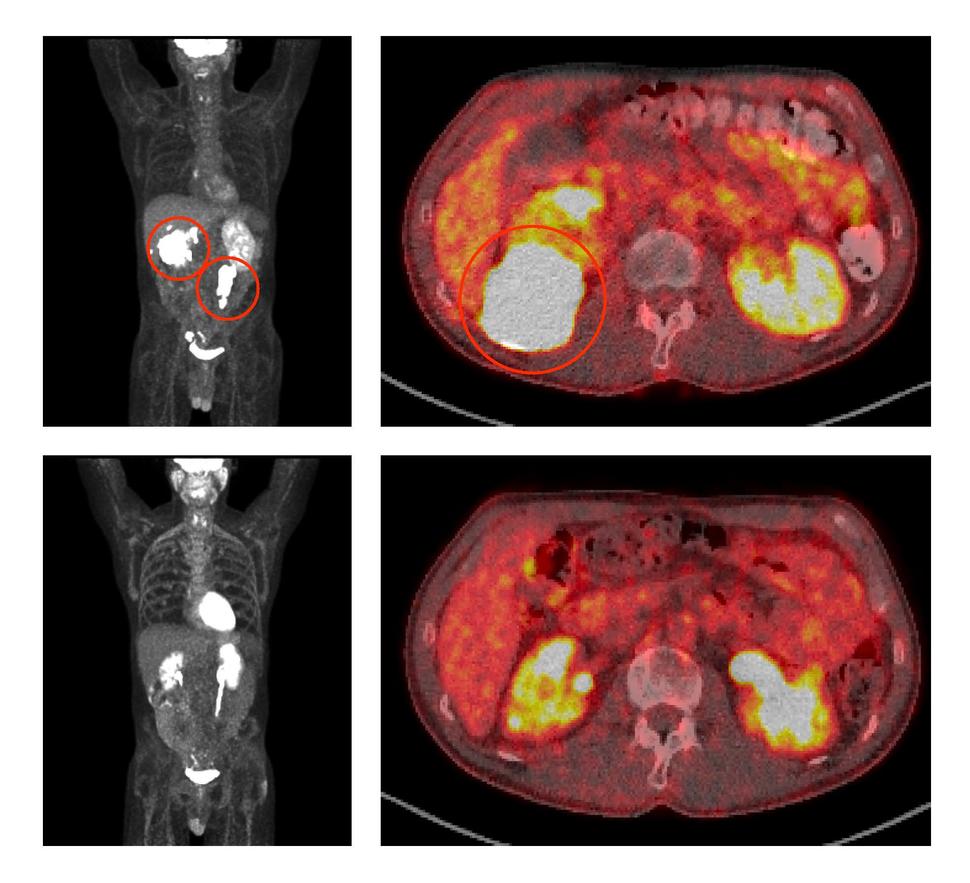

Before treatment with ViPOR, full-body and cross-sectional PET scans of a patient show large lymphoma tumors (circled in the top two panels). Following treatment, the tumors have disappeared (bottom two panels).

Credit: Center for Cancer Research/National Cancer Institute